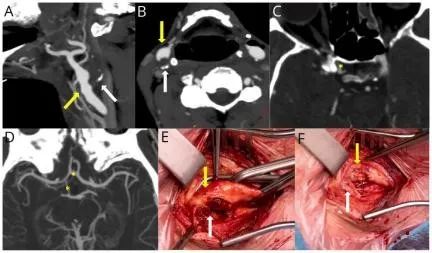

病史摘要:71 岁男性患者,主因双眼眼球突出、右眼疼痛肿胀伴视物模糊 5 个月余入院。5 个月前无诱因出现上述症状,近 1 个月右眼有红色增生物并增大,发病来情绪易暴躁。当地医院诊断为“双眼甲状腺相关性眼病、甲状腺功能亢进症”,治疗后眼部症状无改善且加重。既往有 15 年脑卒中史,行开颅脑室腹腔引流术,有 10 余年高血压史,否认其他慢性、传染疾病史及过敏史等。 诊疗过程:查体见右

双眼白内障

右眼角膜溃疡

压迫性视神经病变